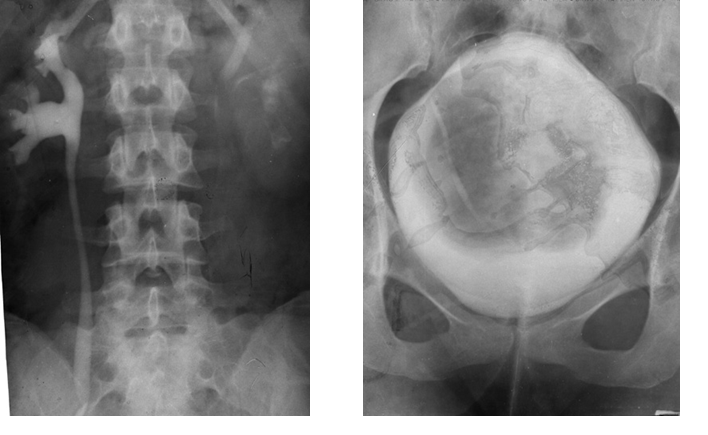

Cistograma Fracturi ale ambelor

ramuri pubiene

Contur neregulat al vezicii urinare Disjunctie

sacro-iliaca dreapta

Hematom pelvian

Disjunctie de simfiza pubiana Disjunctie

de simfiza pubiana

Disjunctie sacro-iliaca stanga Disjunctie sacro-iliaca stanga. Aspect CT

Fractura de coloana anterioara si posterioara Fractura de coloana anterioara si posterioaraAspect CT

asociata cu fractura de aripa iliaca stanga

Fractura de acetabul Fractura de acetabul. Aspect CT